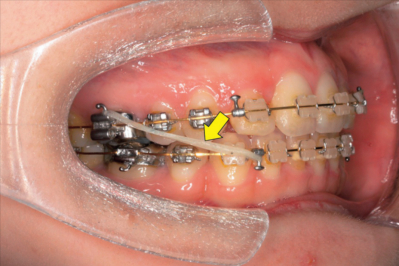

矯正装置装着時の口腔内写真を別に示す。矢印で示す材料の作用で生じる変化はどれか。2つ選べ。

a. 上顎前歯の圧下

b. 下顎大臼歯の圧下

c. 咬合平面角の減少

d. 下顎前歯の舌側移動

e. 上顎骨の前方成長促進